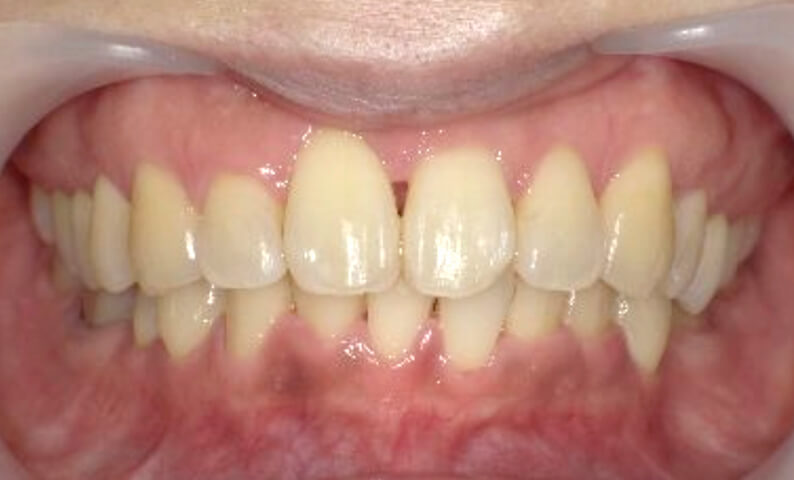

症例_001 下顎だけの部分矯正

治療期間:8ヶ月金額:21万円+税女性前歯のガタガタ下の前歯だけ

| Before | After |

|---|---|

|